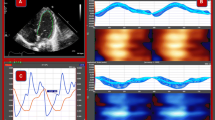

Two-dimensional images of the 4CV were imported into an offline cardiac software program (2D Fetal Cardiac Performance Analysis (2D CPA)), developed by TomTec Imaging Systems, Gmbh (Munich, Germany), using criteria for fetal applications that have been previously described [14]. The endocardial end-diastolic and end-systolic borders were defined using the quiver technique [15]. From 49 speckle tracking identified points distributed along the end-systolic and end-diastolic length of the ventricular endocardium, the pixel coordinates for each point were imported into a programed Excel spreadsheet that computed the measurements described below (Fig. 1).

End-Diastolic Measurements of the Size and Shape of the Right and Left Vernicles in a Fetus with D-Transposition. A Four-chamber view. B Measurements of the 24-segment transverse widths from the base (S1), mid-chamber (S12) and apex (S24, and the length (L). C Left outflow tract illustrating the main pulmonary originating from the left ventricle (LV). D Three-vessel tracheal view demonstrating the aorta originating from the right ventricle (RV). LA left atrium. RA right atrium, PV pulmonary valve, AV aortic valve, MPA main pulmonary artery, RPA right pulmonary artery, LPA left pulmonary artery, MPA, SVC superior vena cava, T trachea

From the 4-chamber view (Fig. 1A) the RV and LV end-diastolic area, mid-chamber length, and 24-segment transverse widths (Fig. 1B) were measured and regressed against gestational age as the independent variable to compute the corresponding D-TGA z-scores using equations of the mean and standard deviation previously published from the control group [11, 13].

The 24-segment sphericity index was computed by dividing the end-diastolic length by each of the end-diastolic 24-segment widths (Fig. 1B) [12].

Ventricular contractility was defined as non-volume measurements of the ventricles and categorized as follows: (1) global contractility, (2) longitudinal contractility, and (3) transverse contractility (Table 1). Global contractility was ascertained by measuring the fractional area change (Table 1, Fig. 2A) [8]. Longitudinal contractility was divided into two sections: (1) global, free, and septal wall longitudinal strain (Table 1, Fig. 2B–D) [6] and (2) free and septal wall annular plane systolic excursion (Table 1, Fig. 2E and F) [10]. Transverse contractility, defined as transverse fractional shortening, was computed for each of the 24-transverse width segments (Table 1, Fig. 2G). [7]

Graphic illustrations of Ventricular Measurement Derived from Speckle Tracking Analysis of the Right and Left Ventricles. A Illustrates the systolic and diastolic areas used to compute the fractional area change. [8] B, C, and D Illustrate the global, free wall, and septal strain which are computed by measuring the endocardial end-systolic (red) and end-diastolic lengths (blue). [6] E and F Illustrate the measurements for computing the free wall and septal annular plane systolic excursion (APSE). G Illustrates the 24-segment fractional shortening measurement. H Illustrates the transverse width and length measurements used to compute the end-diastolic and end-systolic volumes using Simpson’s Rule [9]